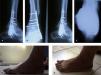

Se documentó la evolución de la paciente a los 3 meses, con resultados muy favorables, sin dolor y radiografías que muestran un proceso de consolidación activo con muy buenos resultados (figura 4).